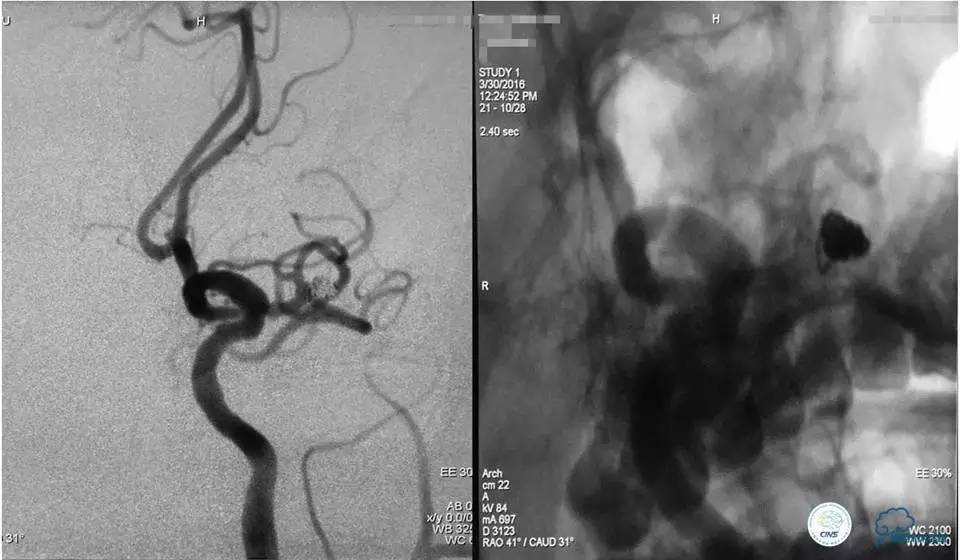

入院后造影检查:

右侧椎动脉正(a)、侧(b)位造影显示右侧椎动脉V4段重度狭窄及右侧椎动脉V4段动脉瘤,狭窄位于瘤颈处,狭窄率为70%,动脉瘤大小为6.99mm×5.95mm,瘤颈宽为3.58mm。